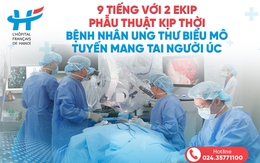

9 tiếng - 2 ekip phẫu thuật kịp thời bệnh nhân ung thư người Úc

27/02/2024 15:30

Vừa qua, tại bệnh viện Việt Pháp Hà Nội (HFH), một bệnh nhân người Úc (63 tuổi) ung thư biểu mô tuyến mang tai đã được phẫu thuật thành công.